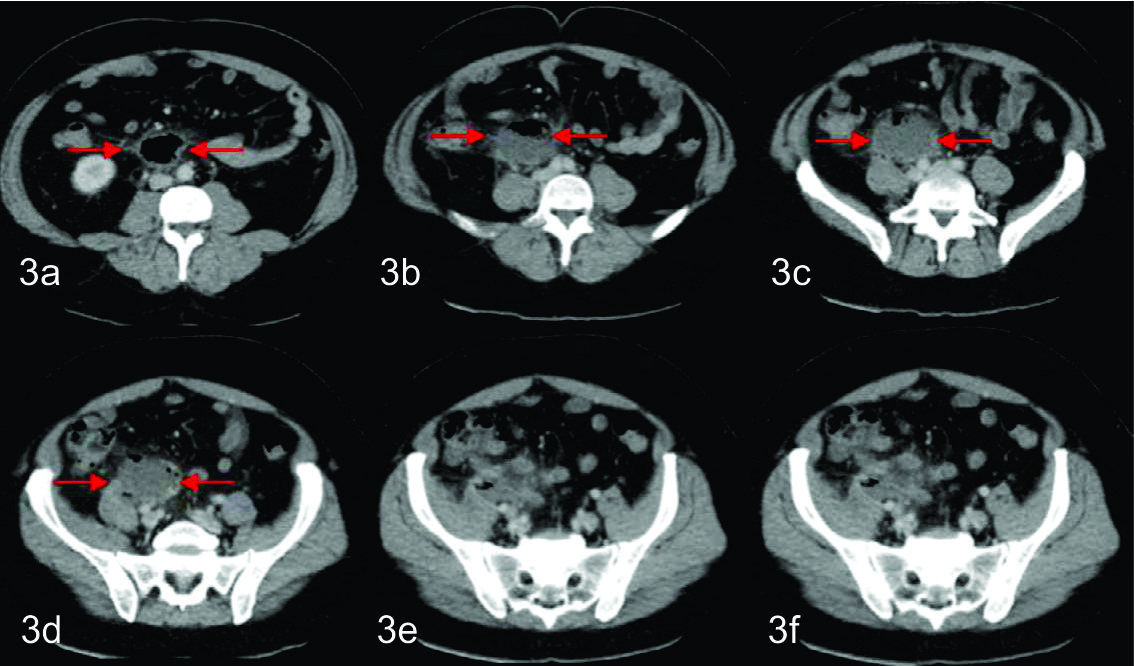

En el control tomográfico posterior, realizado a los 7 días del procedimiento, se reconoce el catéter de drenaje ingresando por la pared anterior del abdomen, el cual se dirige caudomedial con su extremo en el fondo de saco de Douglas, sin evidencia de colección residual. Se decide realizar prueba terapéutica cerrando el drenaje. Dada la buena evolución, el mismo es retirado a las 48 hs.

En los cortes más caudales se reconoce al ciego en su topografía habitual y de él se observa emerger de su pared posterior, al apéndice cecal, el cual es de aspecto patológico, tomando contacto con la colección antes descripta. Con el planteo de apendicitis aguda complicada con colección infectada se discute junto con cirujano tratante la eventual posibilidad de poder realizar tratamiento percutáneo, el cual se determinó que era pasible de ser efectuado en este paciente. Se realizó nuevamente bajo guía tomográfica con el paciente en decúbito supino. Se procedió a topografiar el sitio de abordaje en piel a nivel de flanco derecho y se coloco drenaje multipropósito 12 F bajo técnica de Seldinger, el cual se dejo abierto a bolsa colectora con llave de tres vías. El material obtenido fue purulento, algo hemorrágico, con grumos, del cual se tomaron muestras para análisis bacteriológico, cultivando gérmenes gram negativos. En el control tomográfico posterior, a los cinco días de colocado el drenaje, se necesitó un reposicionamiento del mismo, pudiendo evacuar totalmente la colección residual en la evolución. Luego de 15 días de colocado el drenaje, con levados diarios en los últimos 7 días, una vez resuelta la colección, sin elementos clínicos ni paraclínicos humorales de infección, se decide retirar el drenaje, presentando el paciente una excelente evolución.

En estos dos casos que se presentaron, ambos drenajes fueron colocados bajo guía tomografía debido a la falta de ventana acústica en parte por la profundidad donde se topografiaban las colecciones a drenar.

En la segunda modalidad (Trocar) , se procede a introducir el drenaje armado y mojado sobre una aguja metálica, accediendo de esta forma directamente a la colección. El método de abordaje elegido dependerá básicamente de la ubicación de la colección y la preferencia del operador. En ambos casos se realizo una tomografía computarizada de control confirmando de esta manera el correcto posicionamiento del catéter.

Uno de los pacientes requirió de un reposicionamiento del drenaje al quinto día de colocado, hecho frecuente cuando se drenan colecciones de volúmenes considerables, ya que al al evacuar el liquido y disminuir sensiblemente su tamaño, el drenaje suele quedar posicionado en la periferia de la colección.